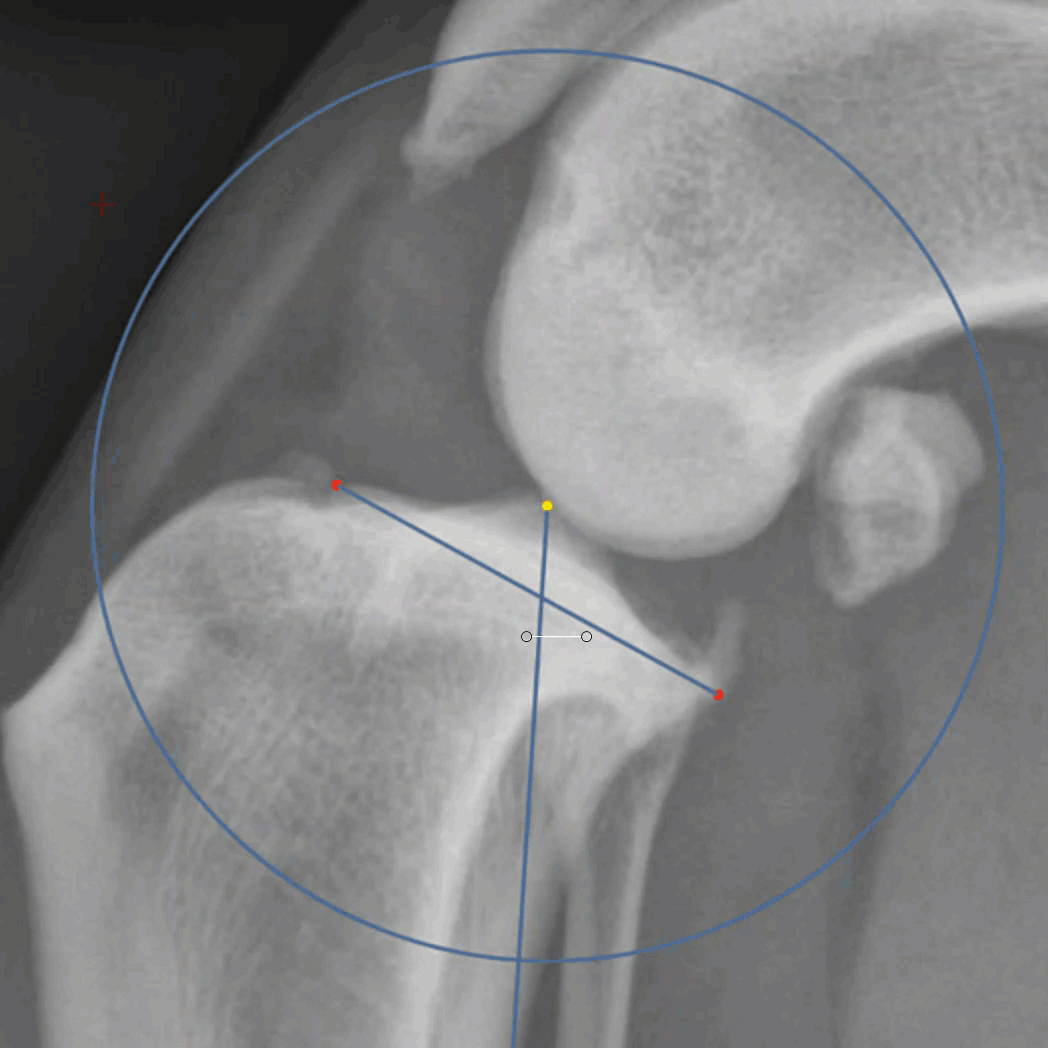

The magnetic cut tool will start with the user performing a single click and drag. Shortly after a line will appear between the initial point and the current location of the mouse. This tool finds the path from the last point to the cursor with the highest contrast. Often this will be along measurement lines. To confirm good locations, where the green line is on the desired path, release the drag to confirm and then click again to start the next segment of the line. This will result in a series of segments of drag and drops to confirm correct locations.

As with all of the cutout tools, the center of rotation can be modified and the 0 degree marker is the grab point from which the cut shape will rotate. click within the shape and drag to move the fragment within the viewport.

Since the Magnetic cut tool snaps to lines, performing a cut along the entire perimeter of the blade is a quick way to cut and rotate a fragment.